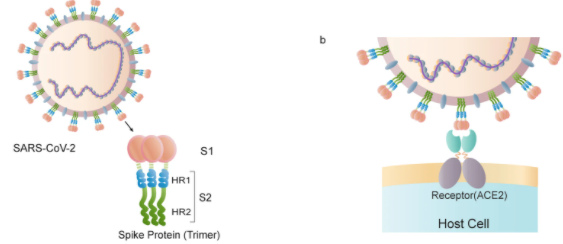

Covid-19 vaccination disease relates to the spike proteins. Spike proteins are found on the surface of SARS-CoV-2. These spike proteins allow the virus to penetrate host cells and cause infection.

The mRNA vaccines contain mRNA created in a laboratory. The mRNA tells the body’s cells to make spike proteins. Our bodies recognise these spike proteins as a threat and the immune system is activated.

In the bloodstream, the mRNA gene goes to the inside wall of the blood vessels. The cells in the blood vessel wall then produce spike proteins. Within hours or days of being injected with the vaccine the immune system will scratch at the inside wall of the blood vessels in order to try to remove the cells that are now producing the spike proteins.

The gene from the mRNA vaccine also invades the lymph nodes and triggers a civil war between the cells that make the spike proteins and the lymphocytes whose job it is to kill cells that make those spike proteins.